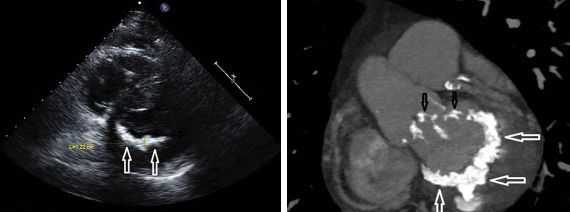

- ЭхоКГ. При УЗИ сердца обнаруживается гипертрофия стенок и расширение полости правого желудочка, наличие трикуспидальной регургитации, снижение показателя систолической экскурсии трикуспидального кольца (TASPE). Для уточнения данных выполняется трехмерная эхокардиография в режиме реального времени (RT3DE).

При диагностическом поиске обнаруживается систолический шум, высокий, скорый пульс, смещение верхушечного толчка. Инструментальные методы обследования при гипертрофической кардиомиопатии включают ЭхоКГ, ЭКГ, ФКГ, рентгенографию грудной клетки, холтеровское мониторирование, поликардиографию, ритмокардиографию. С помощью эхокардиографии выявляется гипертрофия МЖП, стенок миокарда желудочка, увеличение размеров левого предсердия, наличие обструкции ВТЛЖ, диастолическая дисфункция левого желудочка.